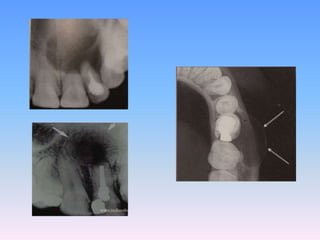

Radiographic features

Classically consists of a well corticated pericoronal radiolucency

which exceeds 5mm when measured from edge of crown to

periphery of lesion on radiographs

• CENTRAL TYPE:

• LATERAL TYPE :

• CIRCUMFERENTIAL

TYPE :

RADIOLOGICAL FEATURES

Location :

Dentigerous cyst if found just above the crown

of the involved tooth, which usually is the

mandibular or maxillary third molar or the

maxillary canines.

 Cyst attaches to the cementoenamel junction.

i. Radiograph of a lateral periodontal cyst lying between the mandibular

premolar teeth.

ii. The margins are well corticated, indicative of slow enlargement.